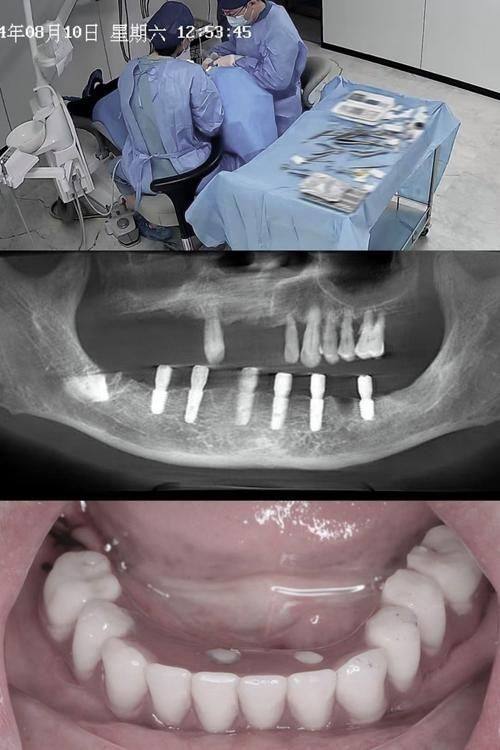

即刻负重种植:种植体植入后可即刻佩戴临时牙冠,术后快速修复咀嚼功能,满足患者对治疗效率的高要求。

王先生:即刻负重种植

"因为工作忙,我希望种牙能尽快修复功能,了解到昆明市口腔医院种植科的即刻负重技术后就来了。谢亮焜医生给我做了即刻负重种植,术后当天就戴上了临时牙冠,第二天就能正常吃饭,完全不影响工作。医生诊疗过程特别耐心,解答了我所有的疑问,后续复诊也特别及时,现在恒久牙冠戴了三个月,用着特别舒服,真心推荐这家医院。"